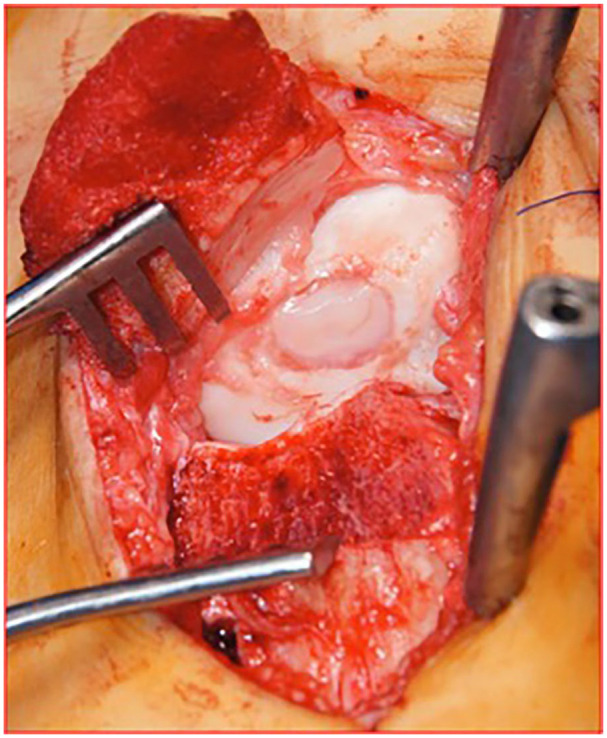

Abstract Image